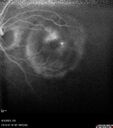

West Nile Virus Multifocal Choroiditis with later CNVM67 views77 year old female with vision loss in the left eye treated with Anti-VEGF